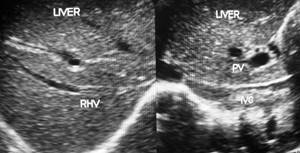

Hepatic vena cava syndrome (HVCS) a bacterial infection-induced disease of the hepatic portion of inferior vena cava that results in hepatic venous outflow obstruction (HVOO) is endemic in the country.26 The disease is seen predominantly among people of poor socio-economic background. .HVCS is a chronic disease with a long asymptomatic course. The initial lesion in the disease in inferior vena cava is a localized thrombophlebitis or endophlebitis at the site of hepatic vein openings which on resolution converts it to stenosis with development of cava-caval collaterals.27,28 The disease is diagnosed by ultrasonography and color Doppler (US/CD) examination of inferior vena cava and liver (Figure 1a&1b).29 An important clinical feature of the disease is the occurrence of recurrent acute exacerbations precipitated by bacterial infection. Acute exacerbation is marked by neutrophil leukocytosis, elevated level of C-reactive protein and ESR with mild elevation of transaminases and/or bilirubin. Severe acute exacerbation occasionally occurs with sudden development of ascites with or without pleural effusion associated with simultaneous development of bacterial peritonitis.30 Patients with recurrent acute exacerbations develop mild splenomegaly with hematological features of hypersplenism commonly neutropenia and/or thrombocytopenia.31 Acute exacerbation results in further deposition of thrombophlebitis at the site of the lesion that extends along its posterior wall and into intra-hepatic veins. Past episodes of acute exacerbations are indicated by presence in inferior vena cava of thrombophlebitis of different ages (Figure 2a–2d). Subsequent organization of the thrombophlebitis leads to development of a membrane in inferior vena cava in a few patients (Figure 2e). Recurrent acute exacerbations result in the development of thrombophlebitis, intimal thickening and stenosis of intra-hepatic veins and increase in echo-texture of the liver parenchyma that progress to cirrhosis (Figure 2e–3b). Medical management of the disease has been described.32

Figure 2a Recurrent acute exacerbations of HVCS: Inferior vena cava showing thrombophlebitis of different ages.

Figure 2b Severe Acute Exacerbations: Inferior vena cava showing thrombophlebitis of different ages with large recent thrombus at the mouth of hepatic veins causing ascites.

Figure 2c Development of chronic liver disease from recurrent acute exacerbations. It shows thrombophlebitis of different ages in inferior vena cava and thrombophlebitis and intimal thickening in Intra-hepatic veins with increase echo-texture of liver parenchyma.

Figure 2d Color Doppler ultrasonography: Show stenosis of inferior vena cava at the site of hepatic vein opening and distal dilated segment of vein with old organized thrombophlebitis. Organized fibrosed thrombi on posterior wall show development of capillaries. Liver parenchyma has increased echo-texture.

Figure 2e Development of membrane in inferior vena cava: The thrombophlebitis in inferior vena cava has organized into a membrane just distal to the opening of middle hepatic vein. Liver parenchyma shows feature of early cirrhosis.

Figure 2 Recurrent Acute exacerbation of Hepatic Vena Cava Syndrome is indicated by presence of thrombi of different ages in inferior vena cava and diffuse presence of thrombus or intimal thickening of intra-hepatic vein and progressive increase in echo-texture of the liver parenchyma .